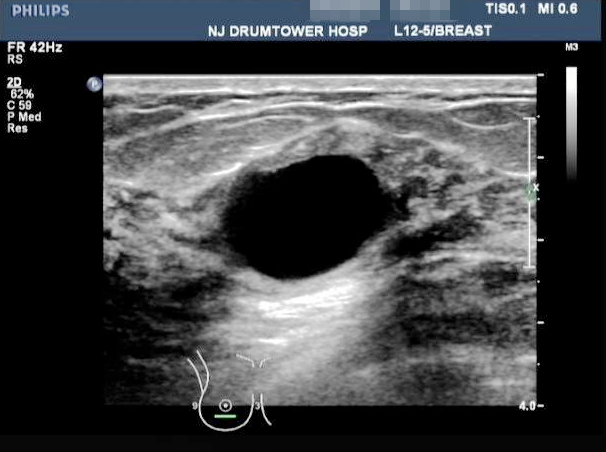

乳腺囊肿在B超下的影像表现

乳腺囊肿是乳腺结节的一种,它最大的特征是其内容物为液体,在彩超下表现为无回声结节。而乳腺增生是一种女性常见的生理现象。表现为乳房的胀痛以及乳房质地的不均一,它和月经周期、情绪压力有关。纤维腺瘤是良性的乳腺结节,年轻女性比较好发。直径较大的纤维腺瘤可能可以在体表触摸到,直径较小的就只能通过彩超检查才能发现了。

乳腺囊肿,以至于其他乳腺的结节,目前都没有发现明确有因果关系的病因或者致病的诱因。情绪的波动不一定就会导致囊肿的形成。情绪波动对于乳腺增生倒是一个比较常见的诱因。目前学术界比较公认乳腺囊肿的形成多依赖于某种特殊的体质。乳腺囊肿从体表的触感上来说和乳腺其他的结节都是差不多的,所以很难通过手的触摸来分辨乳腺结节的性质。一般是建议采取乳腺彩超超声(B超)的检查来判断。如果超声报告提示“无回声”或者“囊性”的结节,那么就是乳腺囊肿。